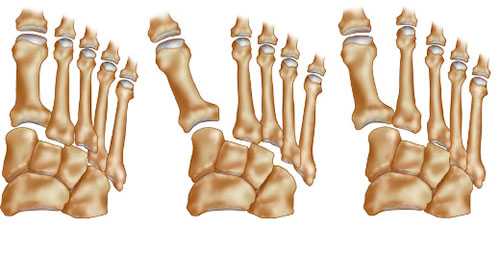

(Слева) На рисунке тыльной поверхности стопы изображен односторонний переломовывих сустава Лисфранка. Показаны латеральное смещение 1-5 плюсневых костей, поперечный перелом основания 2-й плюсневой кости и разрыв связки Лисфранка.

(Справа) На рисунке тыльной поверхности стопы изображен частичный переломовывих сустава Лисфранка. Первая плюсневая кость расположена правильно, в то время как 2-5 плюсневые кости смещены латерально. Связка Лисфранка разорвана. (Слева) При рентгенографии среднего отдела стопы в боковой проекции определяются вывихи 1-5 предплюсне-плюсневых суставов, ладьевидно-клиновидного сустава и сустава Шопара, возникшие у мотоциклиста в результате дорожно-транспортного происшествия. Кроме того, выявляется множество мелких костных фрагментов.

• Односторонний: латеральное смещение всех плюсневых костей

• Дивергентный: 1-я плюсневая кость смещена медиально, 2-5 плюсневые кости-латерально

• Частичный: вывих некоторых предплюсне-плюсневых суставов

• Изолированный: вывих одного предплюсне-плюсневого сустава

• Продольный: медиальное смещение 1 -й плюсневой кости и предплюсне-плюсневого сустава относительно оставшейся части сустава Лисфранка